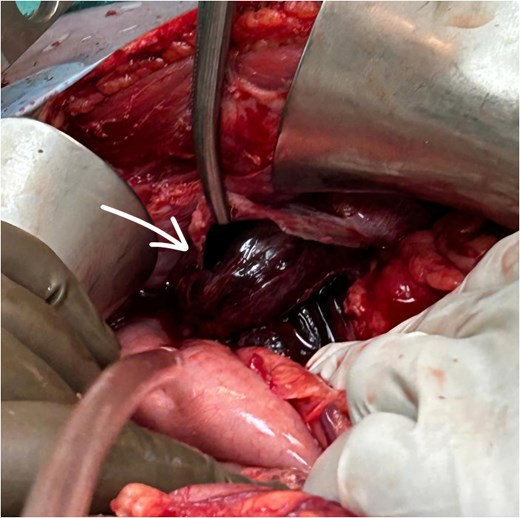

The patient underwent exploratory laparotomy. Left subcostal incision taken, intra-operatively adhesions were noted over the left hemidiaphragm near the defect, and herniation of the splenic flexure of colon along with part of stomach and greater omentum. The part of omentum was found gangrenous (Figs 3 and 4) and rest of the herniating contents was healthy and viable. The herniating content was repositioned in abdomen after adhesiolysis with omentectomy and primary repair of the left diaphragmatic defect using Prolene 1-0 RB (Fig. 5) after refreshening edges of the defect which were later sent for biopsy. The procedure was uneventful. One chest tube was placed in the left hemithorax and one abdominal draining tube was inserted in the subdiaphragmatic space.